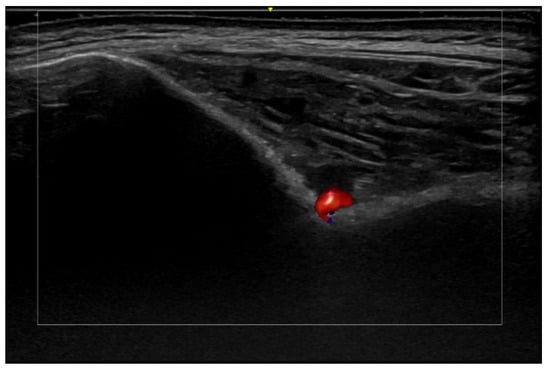

- Di Battista, M.; Vitali, S.; Barsotti, S.; Granieri, G.; Aringhieri, G.; Morganti, R.; Dini, V.; Della Rossa, A.; Romanelli, M.; Neri, E.; et al. Ultra-high frequency ultrasound for digital arteries: Improving the characterization of vasculopathy in systemic sclerosis. Semin. Arthritis Rheum. 2022, 57, 152105. [Google Scholar] [CrossRef] [PubMed]